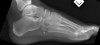

X-ray에서는 종입방관절면을 따라 골절선을 볼 수 있습니다.

초기의 X-ray에서는 발견할 수 없어도 골위축증이 시작되는 3주일 후의 X-ray에서 발견되는 경우가 있습니다.

X-ray : 입방골 압박골절(Cuboid fracture, Nutcracker fracture)